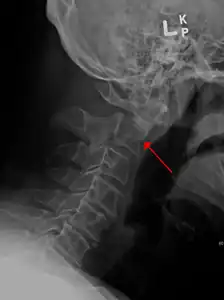

Fracture of dens

Fractures of the dens, not to be confused with Hangman's fractures, are classified into three categories according to the Anderson Alonso system:

• Type I fracture - Extends through the tip of the dens. This type is usually stable.

• Type II fracture - Extends through the base of the dens. It is the most commonly encountered fracture for this region of the axis. This type is unstable and has a high rate of non-union.

• Type III fracture - Extends through the vertebral body of the axis. This type can be stable or unstable and may require surgery.